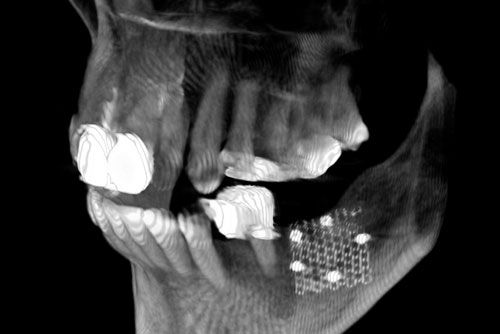

Implantologie

Augmentation

Sinuslift

Ein Zahn-Implantat ist wie eine künstliche Zahnwurzel aus Titan oder Keramik, die in den Kieferknochen eingesetzt wird.